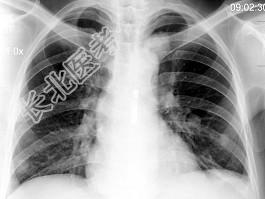

- 单项选择题男,38岁, 咳嗽、胸痛、咯血1天,X线检查如图, 最可能的诊断是 ( )